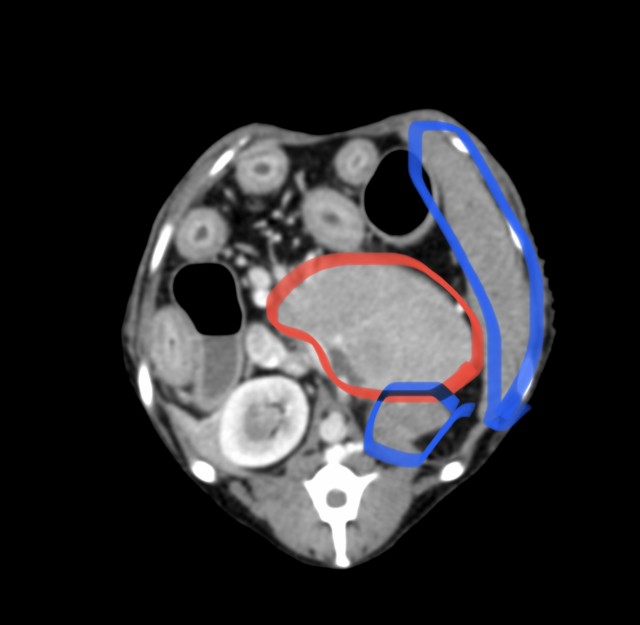

CT検査では、腫瘤は脾臓と接しているものの脾臓からの発生ではなく、その他の腹腔内臓器で唯一、左側の副腎が確認できないため副腎腫瘤と診断した。

腫瘤は大きく、かつ後大静脈との癒着も疑われるため、手術による摘出は極めて困難であると判断した。